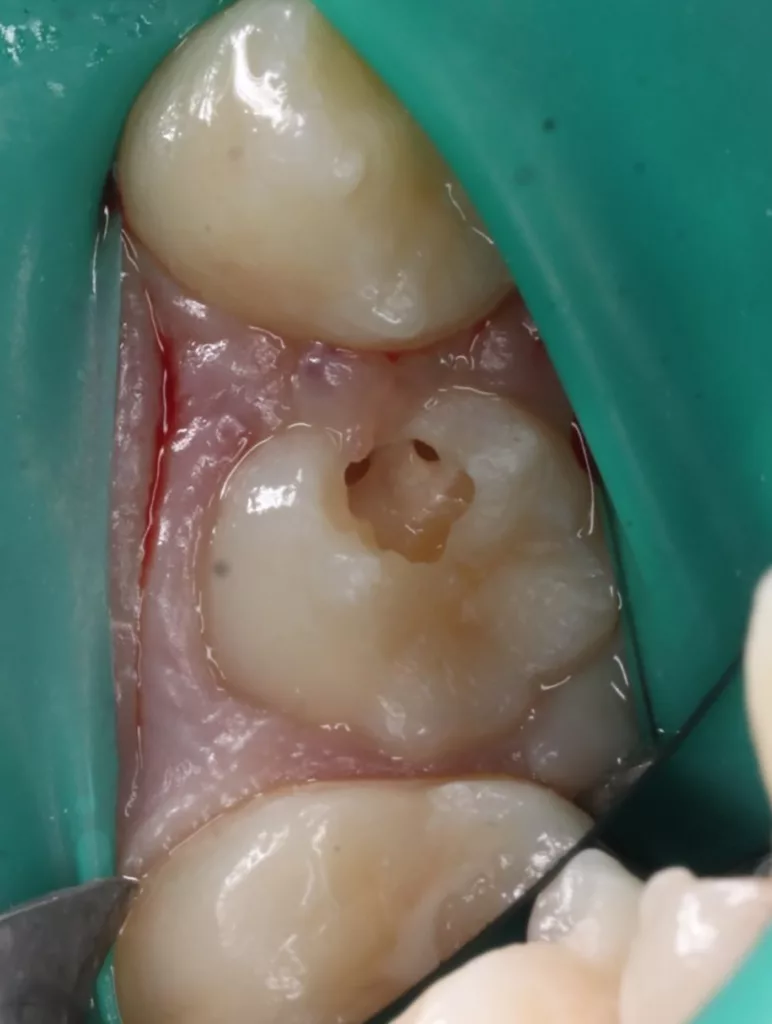

Das siebenjährige Mädchen wurde von einer Kollegin zur Behandlung einer atypischen intrakoronalen Aufhellung im Kronenbereich des nach Durchbruch befindlichen symptomatischen Zahnes 46 überwiesen (Abb. 20). Anamnestisch bestanden seit zwei Tagen kurzintervallige Spontan- und Nachtschmerzen, die mit Ibuprofen 40 mg/ml Kindersirup behandelt wurden. Das Röntgenbild zeigte einen umfangreichen runden Dentindefekt unter intaktem Zahnschmelz, der bis in das Pulpakavum reichte. Daraus ergab sich die Verdachtsdiagnose PEIR des Zahnes 46 (Grad 3 der Läsion nach Seow) in Kombination mit einer akuten Pulpitis. Nach Leitungsanästhesie am Foramen mandibulae mit Septanest 1/100 000 (Septodont, Frankreich) und STA-System (Milstone Scientific, USA) konnte der Zahn mithilfe von Kofferdam (Klammer U67, KSK Dentech, Japan) gut isoliert werden (Abb. 21). Um die ursprüngliche Zahnanatomie zu imitieren, wurde ein Okklusalstempel aus dem flüssigen Kofferdam OpalDam (Ultradent, Frankreich) und einem Microbrushapplikator angefertigt.

Der PEIR-Defekt schimmerte unter der lingualen Querfissur deutlich dunkler durch (Abb. 21), sodass die Entscheidung getroffen wurde, den Defekt an genau dieser Stelle zu eröffnen (Abb. 22). Das resorbierte intrakoronale Weichgewebe, das die Läsion nur zum Teil füllte, konnte dann gut visualisiert werden (Abb. 22). Kariös verändertes Dentin wurde nicht gefunden. Nach Eröffnung des Pulpahorns sah die Pulpa blass und avaskulär mit Anzeichen einer geringen Blutung aus (Abb. 23). Die komplette Kronenpulpa wurde bis zur Höhe der Kanaleingänge mit einem runden Diamantbohrer unter Wasserkühlung entfernt. Vor und nach der Prozedur wurde die Läsion zuerst mit 1%igem NaOCl und anschließend mit physiologischer Kochsalzlösung gespült. Die Blutung stoppte innerhalb von zwei Minuten vollständig, die Wurzelpulpa erschien gesund, regulär vaskularisiert und sauber (Abb. 24). Es wurde eine reversible Pulpitis diagnostiziert. Die Abdeckung der Wurzelpulpa erfolgte mit einem hydraulischen Kalziumsilikatzement (Rootdent, Technodent), der mit dem Glasionomerzement Fuji II LC (GC, Japan) als temporäre Füllung abgedeckt wurde. Die Platzierung des MTA-Zements wurde abschließend mittels einer Röntgenaufnahme überprüft (Abb. 27). Nach zwei Wochen war die junge Patientin komplett beschwerdefrei. Unter erneuter Trockenlegung mit Kofferdam wurde die adhäsive koronale Restauration mit Komposit Estelite ASTERIA OCE, A2B und Universal Flow AO2 (Tokuyama, Japan) mithilfe eines vorab angefertigten Okklusalstempels erstellt (Abb. 25 und 26). Ein Jahr später kam die Patientin beschwerdefrei zur Nachkontrolle. Das Röntgenbild (Abb. 28) zeigte keinen pathologischen Befund sowie eine physiologische Weiterentwicklung des Wurzelwachstums in Länge und Dicke der Wurzelwände.